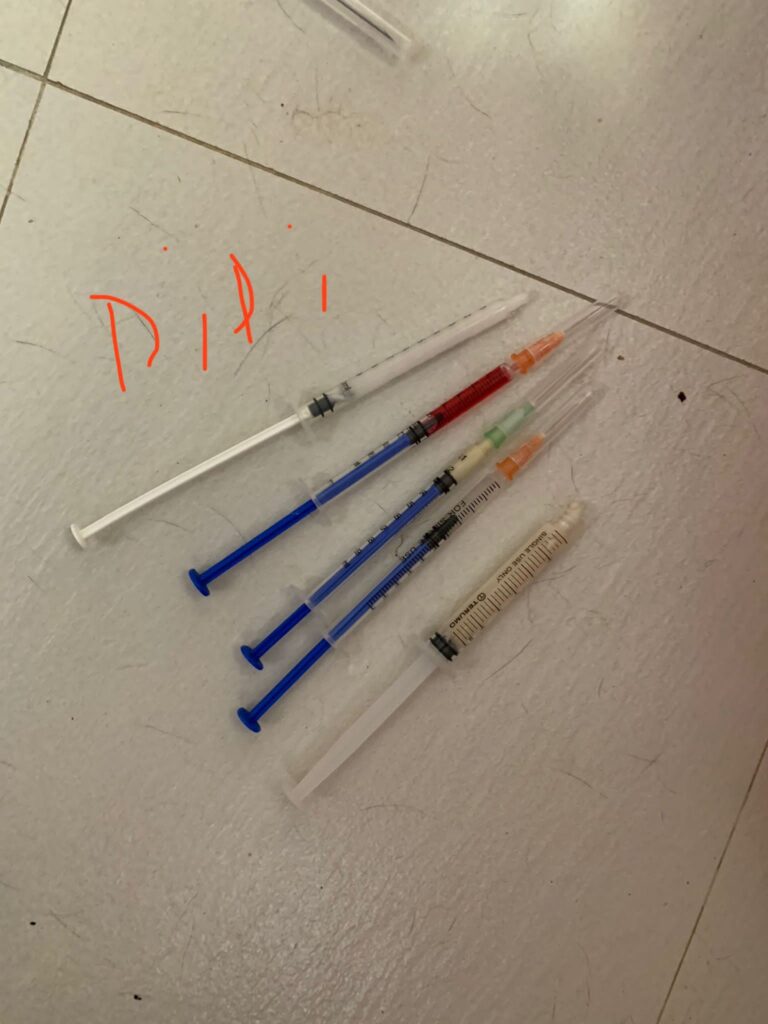

Prepare his fercosang jab to be given Tmr

11Am+: given Subcut, b com n b12 and fercosang. He is still on f patch, wipe his face